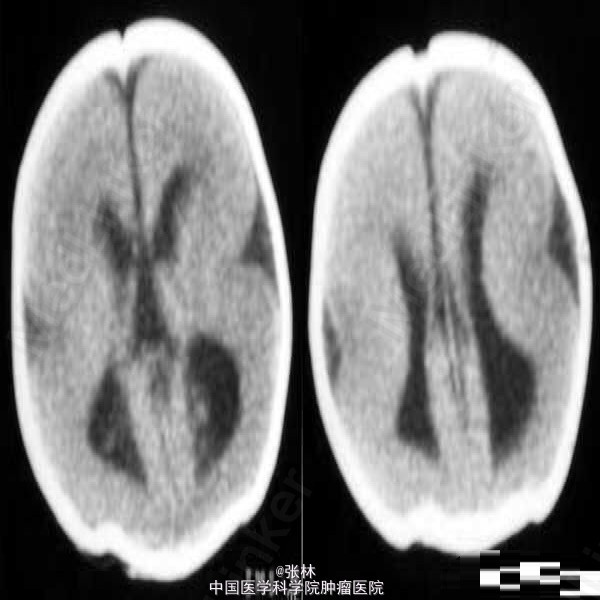

【临床病史】:患儿,F/0.5Y。癫痫,近一个月来频发。五官尚可,头颅大小与同龄儿相比稍小,智力低下(平时家人逗小孩时目光及动作迟缓)。 【影像表现】:显示双侧大脑半球皮层明显增厚、表面光滑、无脑回及脑沟,皮层下白质稀少。双侧外侧裂变浅、凹陷,整个双侧大脑半球呈“8”字形表现,脑室系统扩大。前纵裂增宽、增深,与第三脑室向连通。双侧侧脑室扩大、分离。 【影像诊断】:无脑回畸形伴胼胝体发育不良(Lissencephaly associated with Corpus Callosum dysplasia) 【诊断要点】:无脑回畸形伴胼胝体发育不良 【讨论】:无脑回畸形和/或巨脑回畸形:无脑回畸形指大脑表面光滑,无脑回结构;巨脑回畸形指大脑停留在原始阶段,脑回宽、扁。两者仅为畸形成度不同,可同时存在于脑的不同部位。前者多在顶枕部,后者多位于额部。镜下管前者大脑皮质结构异常,皮质分层不完全或不分层,常见不成熟的神经细胞。后者皮层保留了原始皮层的4曾神经细胞结构,神经细胞分化不成熟。白质中常发现异位的神经细胞,有时呈结节状。 [临床表现] 无脑回畸形患儿在新生儿期常有小头畸形和轻微面部异常,以后表现出智力落后。完全性无脑回畸形者大多在2岁前死亡。巨脑回存活者常有智力低下和癫痫。 [CT表现] 无脑回畸形和/或巨脑回畸形,前者主要表现为脑表面光滑,脑回、脑沟消失,皮层增厚,白质减少。后者主要表现为侧裂变浅、增宽,脑回增宽,皮质增后,内表面光滑,白质减少,患侧脑室系统扩大。此外,无脑回畸形两侧裂变浅,呈“8”字形表现。